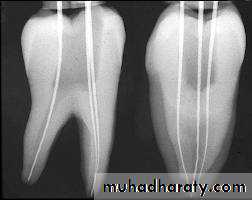

1.Radiographic Methods

Preoperative radiographRadiograph of the tooth with endodontic instrument placed to its tentative working length.

Parallel technique is preferable over bisecting technique